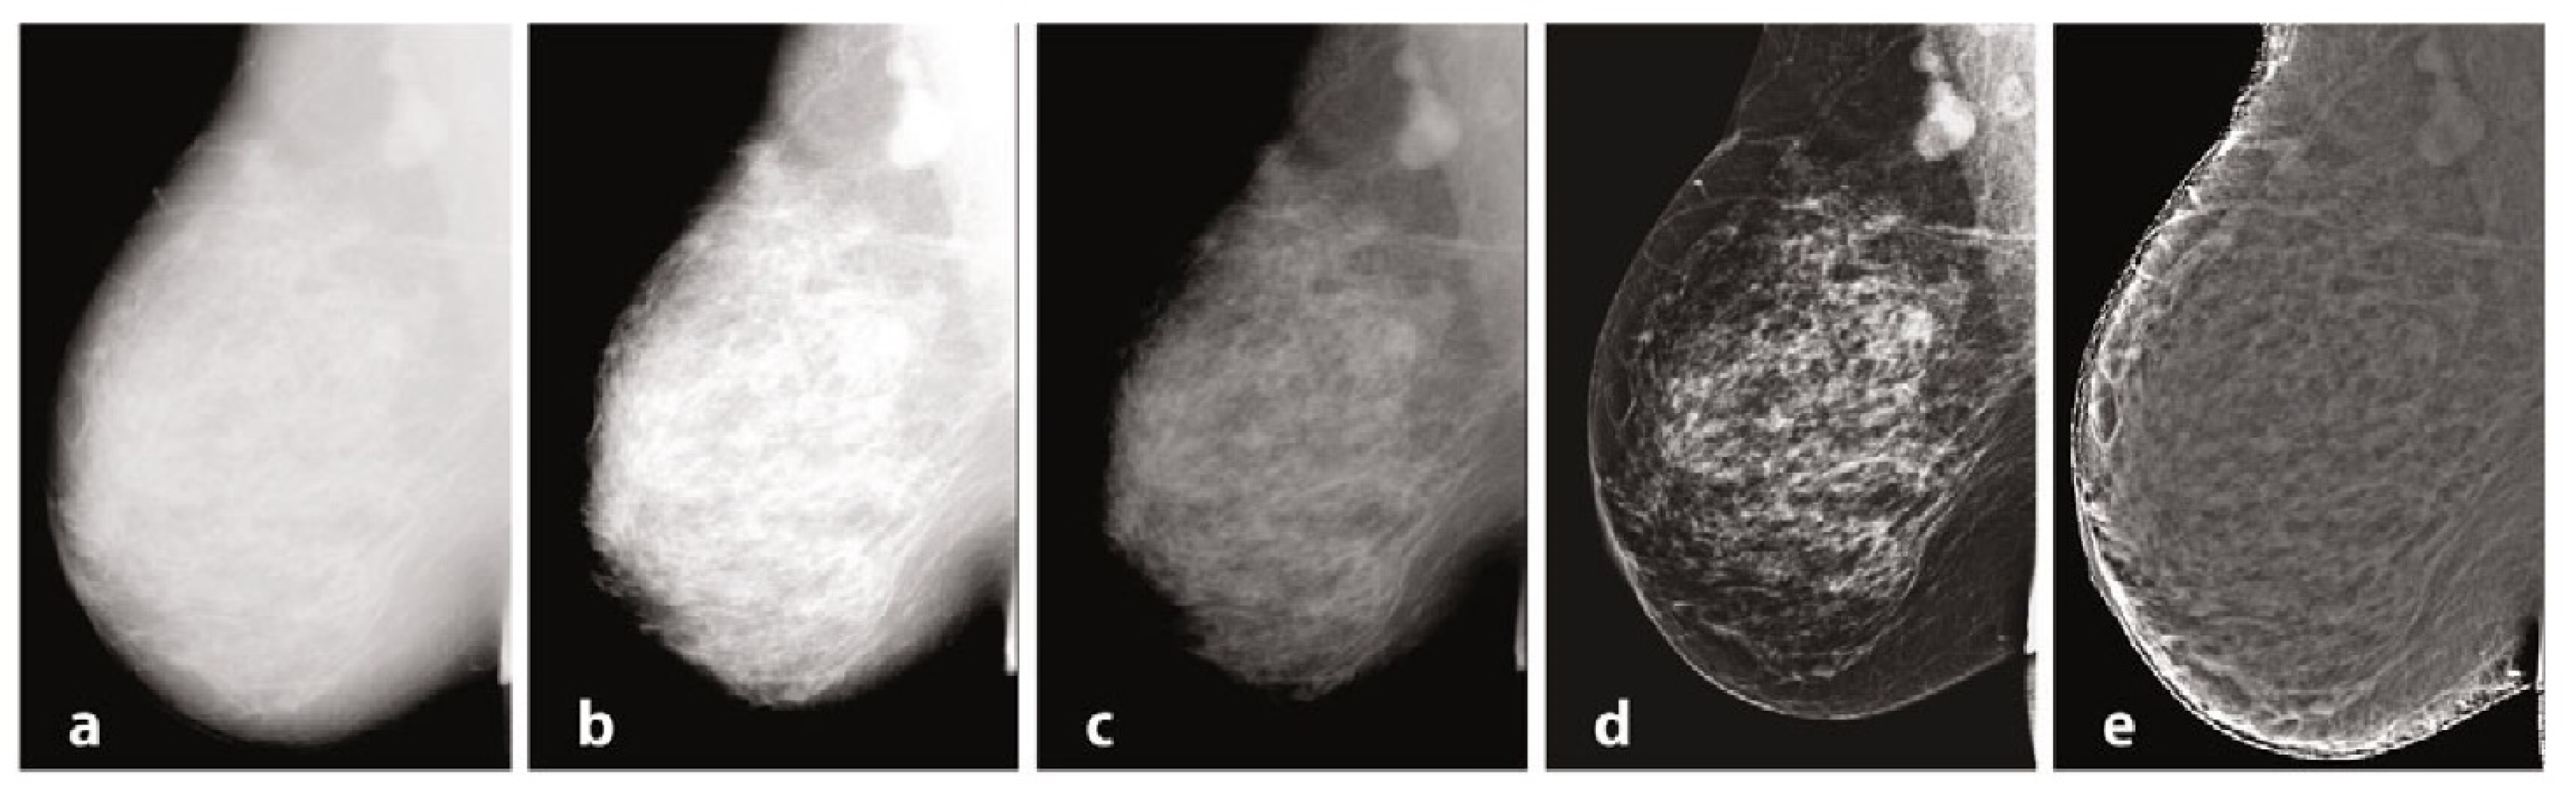

Mammography requires specific characteristics related to the type of instrumentation used and the exposure technique, with geometric parameters and beam energy. Of considerable importance for diagnostics are the characteristics of the detector and intrinsic processing. Processing, in particular, has the primary objective of limiting the effect of the thickness gradient between the part of the organ closest to the chest wall and the more distal part, which will have a decreasing thickness and attenuation [106]. In Figure 1, we provide examples of processing. The raw image (a) has low intrinsic contrast, and (b) varies the windowing by selecting a LUT suitable for more superficial regions, thus enhancing the visualization of peripheral regions with lesser thickness and reduced contrast on the internal tissue at the same time. [107] Also in mammography, as in traditional radiology, it is possible to find the application of LUTs after automatic segmentation of the grey level histogram, relative to tissues of interest: non-compressed adipose tissue, compressed adipose tissue, glandular tissue, and pectoral muscles. Other algorithms exploit unsharp masking, CLAHE histogram equalization, or frequency space analysis. In (c), the contrast was optimized by choosing a LUT suitable for more internal regions, but with a loss of information relative to the more superficial regions. Processing was performed by means of equalization-based processing algorithms, histogram in (d), and peripheral in (e), respectively. The latter is done by first applying a low-pass filter, typically Butterworth, with a cutoff frequency of 0.05 cycles per mm, from which an attenuation map is derived and compared to the original image to even out the thickness-related luminance gradient and allow for a uniform representation of the glandular structure [108].

Figure 1.

Mammography, different elaborations.